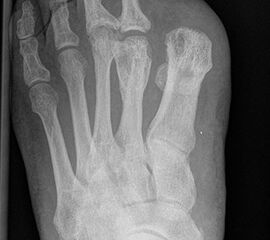

Wird der Ansatz des M. fibularis (peroneus) brevis bei Amputation des 5. Strahls entfernt, kommt es durch das muskuläre Ungleichgewicht zu einer Supination mit Vorfußadduktion und nachfolgend zu einer vermehrten Druckbelastung am Außenrand des Fußes (Abb. 30, 31). Um einer chronischen Ulzeration vorzubeugen, muss die Fehlstellung beseitigt werden, meist durch Transfer der Tibialis anterior Sehne.